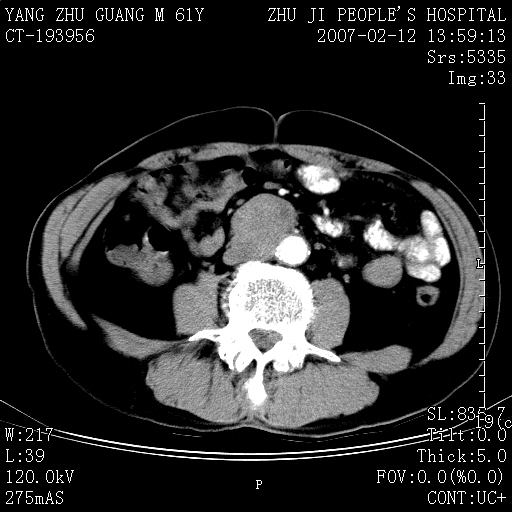

标题: CT6797:后腹膜富血供占位。请会诊。

腹膜后脊柱前方软组织密度肿块,向下包埋下腔静脉,边界清楚,富血供。多考虑:神经源性肿瘤。

脊柱前侧不均匀增强软组织密度影,边界较清,下腔静脉、十二指肠受压稍移位,考虑:腹膜后良性病变1神经源性肿瘤(神经鞘瘤可能性大)2间质瘤

脊柱前侧不均匀增强软组织密度影,边界较清,下腔静脉、十二指肠受压稍移位,考虑:腹膜后占位病变1神经源性肿瘤(神经鞘瘤或副神经节瘤可能)  2间质瘤

主动脉与下腔静脉间软组织肿块,下腔静脉右侧被包埋,轻度强化,肠系膜动静脉受压前移,1淋巴原肿瘤,查其他部位有无肿大淋巴结,2后腹膜肿块,神经原待排.